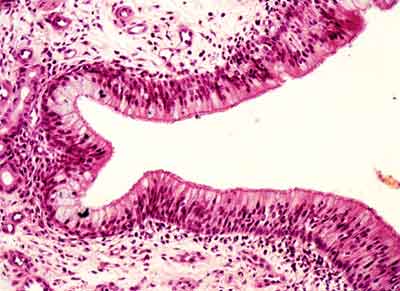

general: sección de las pequeñas

digitaciones de los plexos coroides donde podemos observar un epitelio

de revestimiento cúbico simple, sobre ejes conjuntivos vascularizados.

Los vasos son de diferente tamaño y están revestidos por

epitelio plano simple(endotelio). También se observan calcificaciones

correspondientes a cuerpos de Psamona.

Visión específica: células

isodiamétricas en único estrato, con núcleos redondos

y centrales.